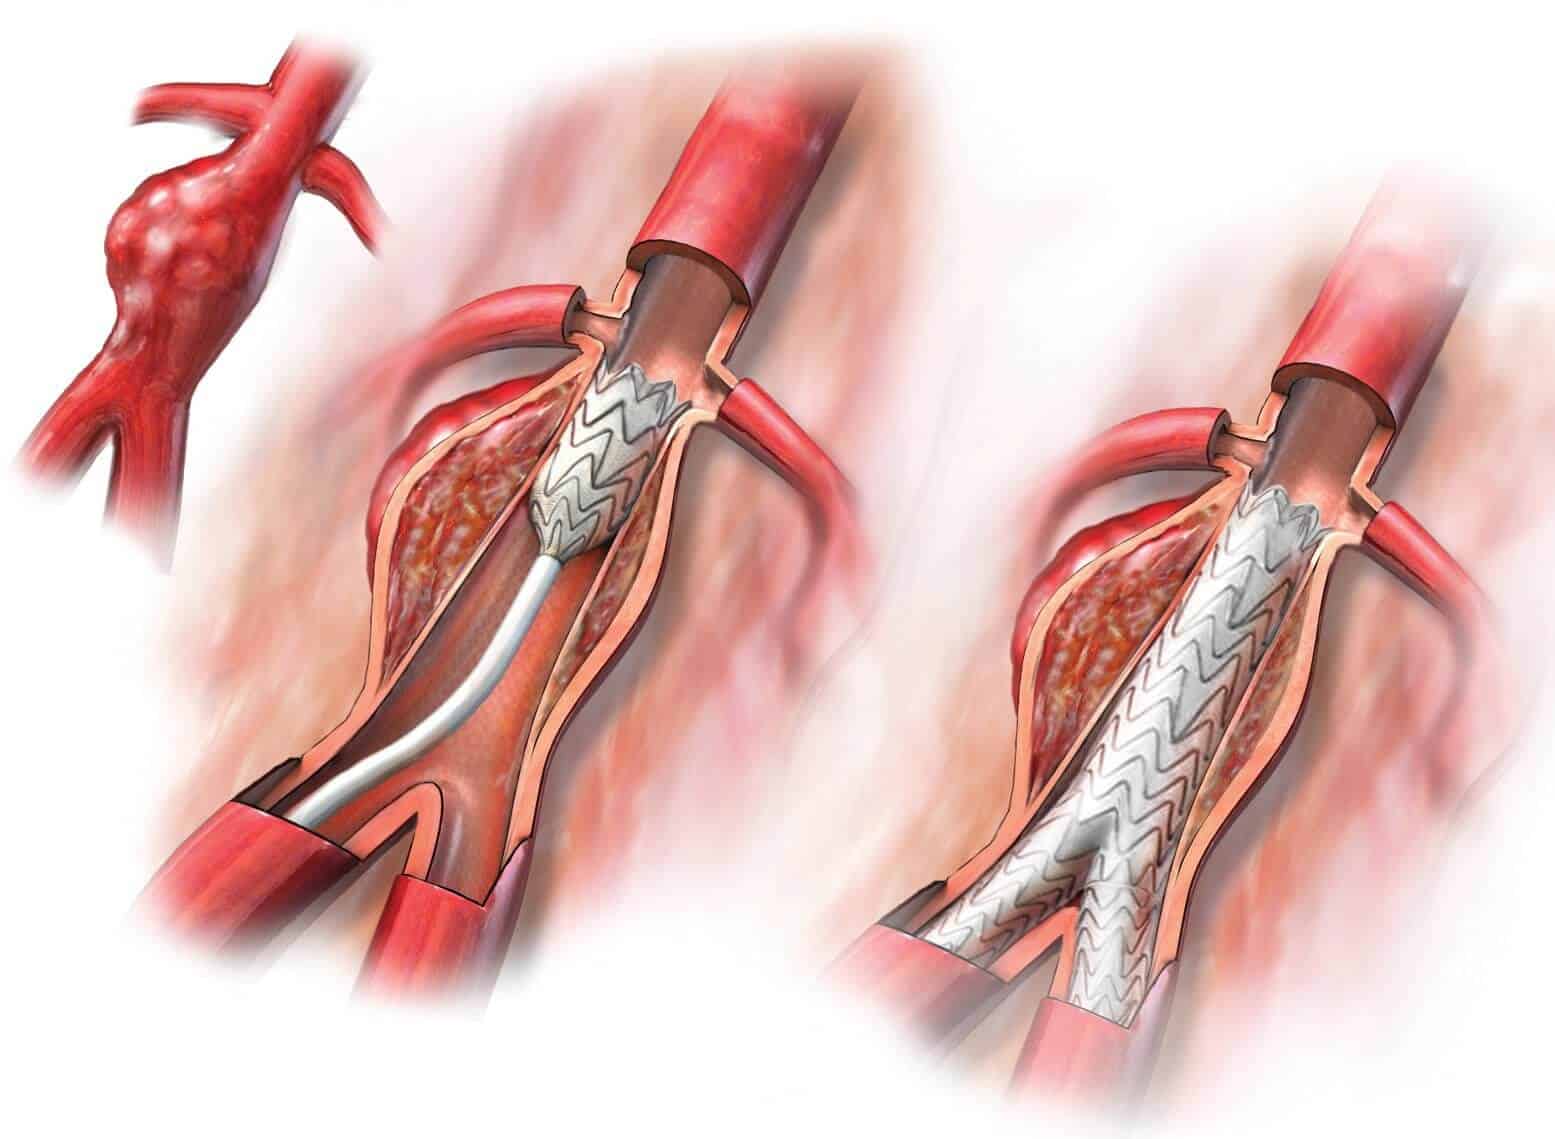

Особенности и диагностика левостороннего кровотока